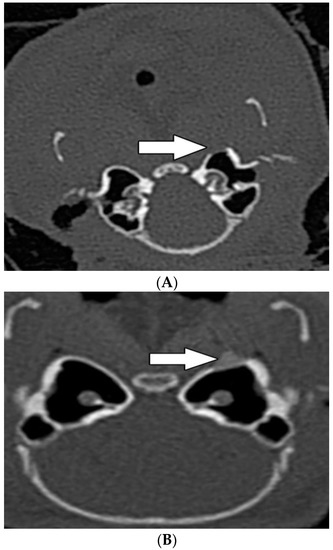

In group A, the areal bone density was estimated in 394 HU ( x ¯ = 390 HU) and “hot spot” bone density in 958 HU ( x ¯ = 960 HU). In group B, the bone density in the area of the implanted material was estimated in 1473 HU ( x ¯ = 1470 HU) and “hot spot” bone density in 1643 HU ( x ¯ = 1640 HU). Compared with group A, both area and “hot spot” bone density were significantly higher in group B (p < 0.0001, p = 0.00276 resp.) (Table 2).

Thickening of the middle ear mucosa was observed in three animals, in one of them the tympanic bulla was filled by fluid (Table 2). CT scans in both groups did not reveal pathological changes in the inner ear (Figure 6A,B).

Figure 6. Radiological examination by HRCT at the level of the tympanic bulla, 60 days after implantation of MSCs in group A (A) and group B (B). Radiological examination by HRCT at the level of the tympanic bulla, 60 days after implantation of MSCs in group A (A) and group B (B). White arrows show the place of the implanted biomaterial into the bone defect.